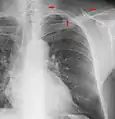

A chest radiograph showing bronchopulmonary dysplasia.